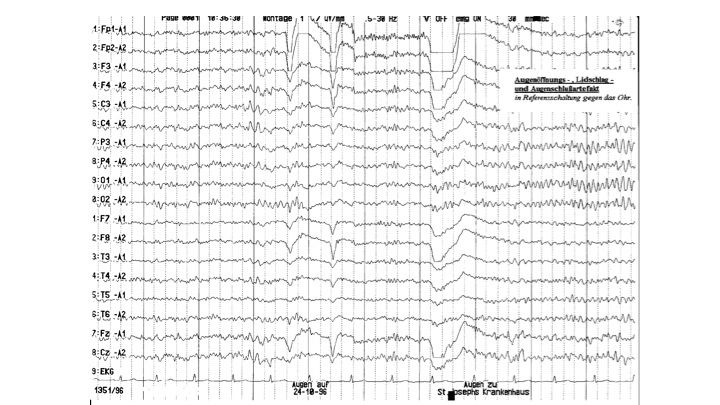

Artefakte im EEG | 8.65 zurück | weiter